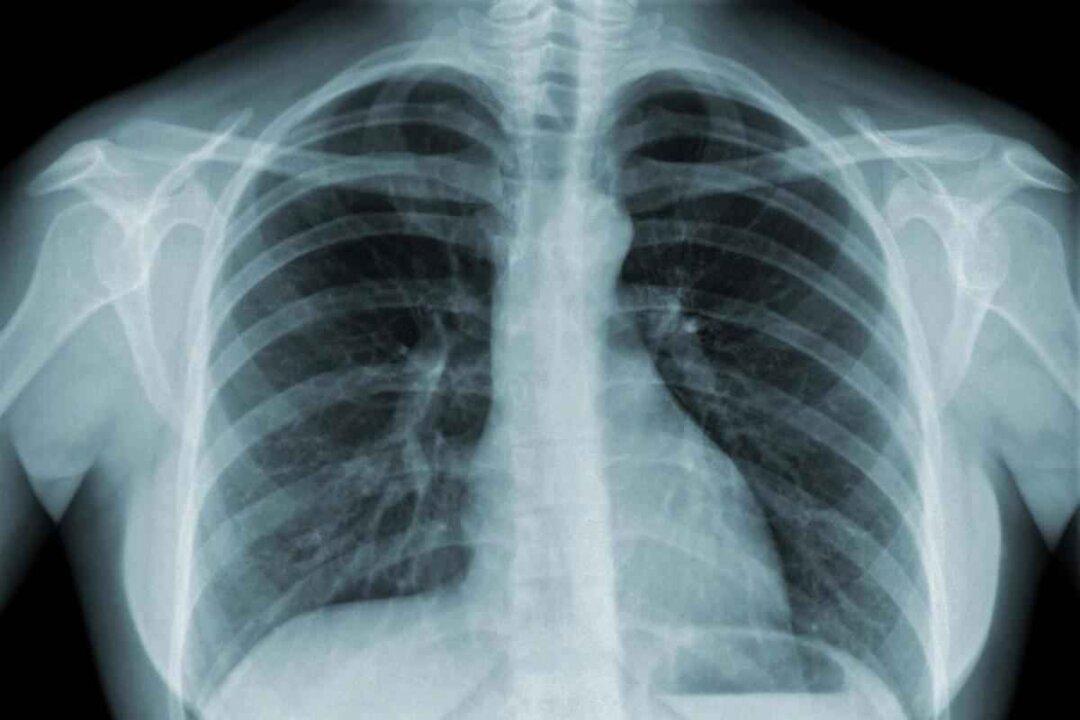

Since the start of the COVID-19 pandemic, many individuals have experienced a decline in lung function following infection. Pyunkang-Hwan, a Korean traditional herbal product that focuses on lung cleansing, has recently gained popularity. Dr. Seo Hyo-seok, the developer of Pyunkang-Hwan, recently held a lecture in Canada, explaining how to enhance the body’s self-healing ability through lung cleansing and nurturing.

Wang Shanqing, a patient with chronic obstructive pulmonary disease (COPD) and pulmonary fibrosis who attended the lecture, shared with a reporter from The Epoch Times that over a year ago, he experienced severe coughing, difficulty sleeping at night, fatigue, and occasional wheezing, to the point where he could not catch his breath. After taking ten bottles of Pyunkang-Hwan, his blood oxygen levels increased from 90 or 91 percent to around 96 percent, and his cough has significantly improved.